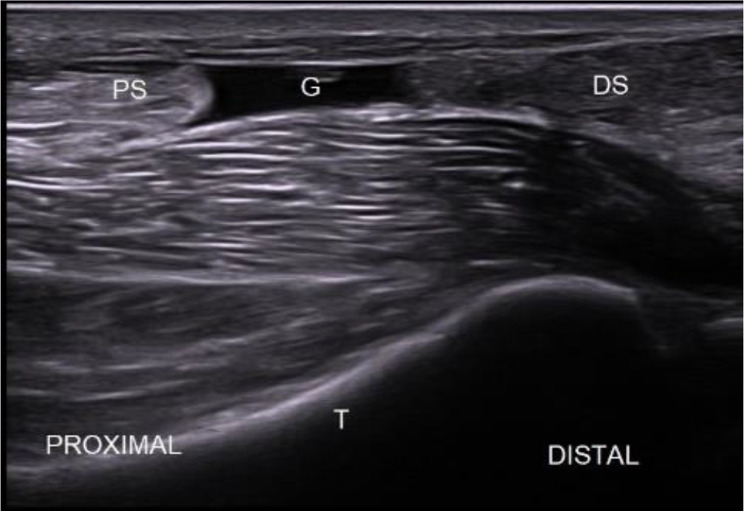

Fig. 6.

Achilles tendon tear: ultrasound image of acute Achilles tendon tear in the sagittal plane. G: gap (tendon lesion); PS: proximal stump; DS: distal stump; T: tibia